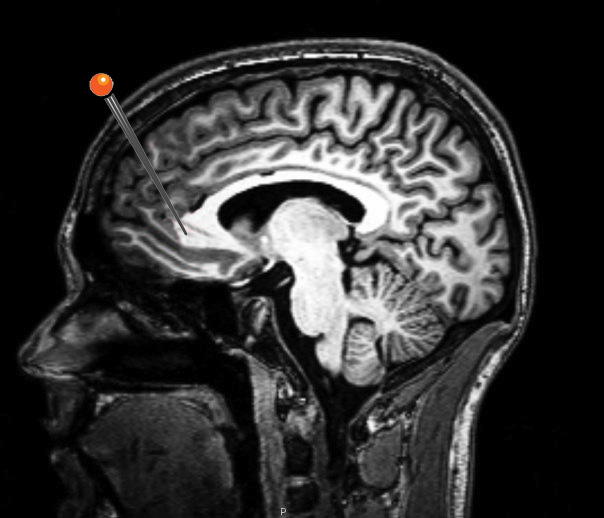

Neurowetenschappers aan de Universiteit van Lelystad hebben een hersengebied ontdekt dat werkelijk helemaal nergens goed voor is. Hoofdonderzoeker Ester Risselada wil de resultaten van het baanbrekende onderzoek in het blad Science presenteren. In de studie vonden de wetenschappers een klein stuk van de parietaalcortex dat ‘op geen enkel van de 62 manipulaties leek te reageren’.

Risselada was erg verbaasd. ‘In onze pilot-studie dachten we eerst dat we een meetfout hadden gemaakt. Het hersengebied reageerde op geen van onze manipulaties. De weken erna probeerden we van alles. We lieten mensen IQ-tests en geheugenoefeningen doen, spreken, luisteren, jongleren, maar er was geen enkele activiteit in het betreffende hersengebied te bespeuren. Uit pure wanhoop trokken we alle registers open: plaatjes van gezichten, erotische plaatjes, kattenfimpjes, plaatjes van geweld, zelfs erotisch geweld, maar er gebeurt werkelijk helemaal niets! Zelfs geen de-activatie. Geen connectiviteit naar andere hersengebieden, zelfs geen voodoocorrelatie. Twee kubieke centimeter compleet nutteloze cortex. Een evolutionaire aanfluiting, als je het mij vraagt.’